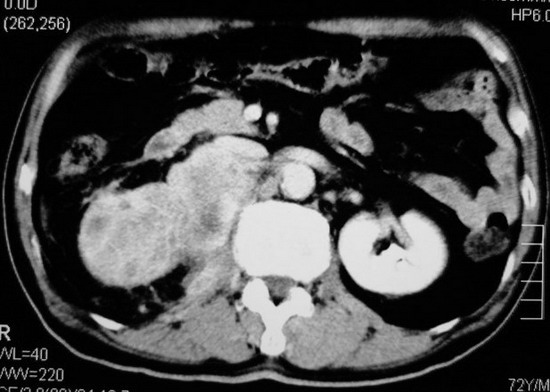

以下是引用杀毒软件在2008-11-17 19:15:00的发言:[br]考虑------右肾癌合并肾静脉---同侧肾上腺受侵可能性大

以下是引用zjzjr在2008-11-17 20:45:00的发言:[br]考虑------右肾癌合并肾静脉---同侧肾上腺受侵可能性大及腹膜后淋巴结转移.